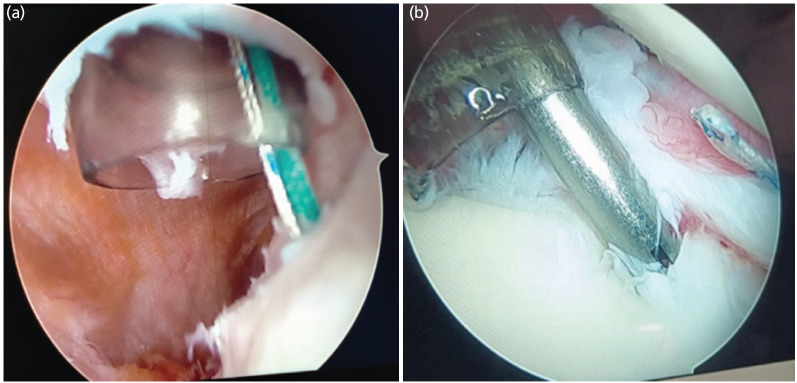

Materials and methods: A total of 36 patients underwent arthroscopic Bankart with Remplissage for recurrent anterior shoulder dislocation, enrolled between February 2022 to December 2023 considering various inclusion and exclusion criteria. Patients were evaluated in post op period for range of motion, oxford shoulder instability score and visual analogue score for pain at intervals of 6 and 12 months.

Results: All patients enrolled had soft tissue with bony Bankart lesion with mean of glenoid bone loss (%) was 11.75% (±3.15%) and all participants had engaging Hill-Sachs lesion. The mean pre-operative OSIS was 19.56 (±2.17) and mean VAS was 5.53 (±0.56). In the post op evaluation, there was no clinically significant decrease in range of motion with mean loss of external rotation of 3.86 (±1.44) at 12 months. The mean OSIS increased to 41.0 and mean VAS decreased to 2.36 at 12 months follow-up which was statistically significant. There was no incidence of dislocation in post op period of 12 months.